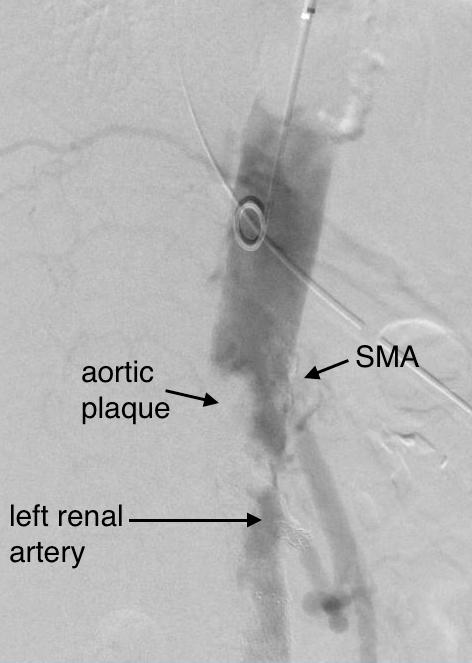

Examination was remarkable for a well nourished young woman in distress with epigastric tenderness. Inflammatory markers were normal and she was on methotrexate and tocilizumab. CTA (above) and duplex showed severe stenoses affecting the origins of the celiac axis and superior mesenteric artery. A composite of the centerlines through these showed the arteries to be critically narrowed at their origins (below), along with a mild to moderate stenosis of the aorta (above). No active inflammation could be seen.

I did feel that revascularizing the SMA was likely to improve her postprandial symptoms, given the paucity of circulation to the gut. I had a discussion about her chest pain and the thought that this was a celiac plexus neuropathy as the result of compression of the celiac plexus by her Takayasu’s disease. Typically, for younger people, I perform a bifurcated graft to the celiac axis and SMA from the distal descending thoracic aorta for younger patients, but I had no intention of replacing her aorta at this time, and wanted to reserve any definitive revascularization of her visceral vessels for a later time if it became necessary. Her pulses were full in the legs and she had no hypertension, renal insufficiency, or claudication. I therefore planned a ilio-mesenteric bypass, as it would preserve planes for a later more definitive operation if necessary, and would address her mesenteric ischemia.

The patient thought this was reasonable and agreed. She underwent a midline laparotomy and I exposed both the SMA and right common iliac artery in the retroperitoneum and tunneled a PTFE graft in a C-pattern in the retroperitoneum. The SMA was diseased proximally under the pancreas and affected by inflammatory scar tissue, and the vessel was thickened as well. The iliac pulse was normal and full and provided excellent inflow.